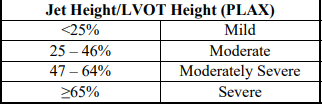

Jet height / LVOT Height (PLAX)

mild

moderate

moderatley severe

severe